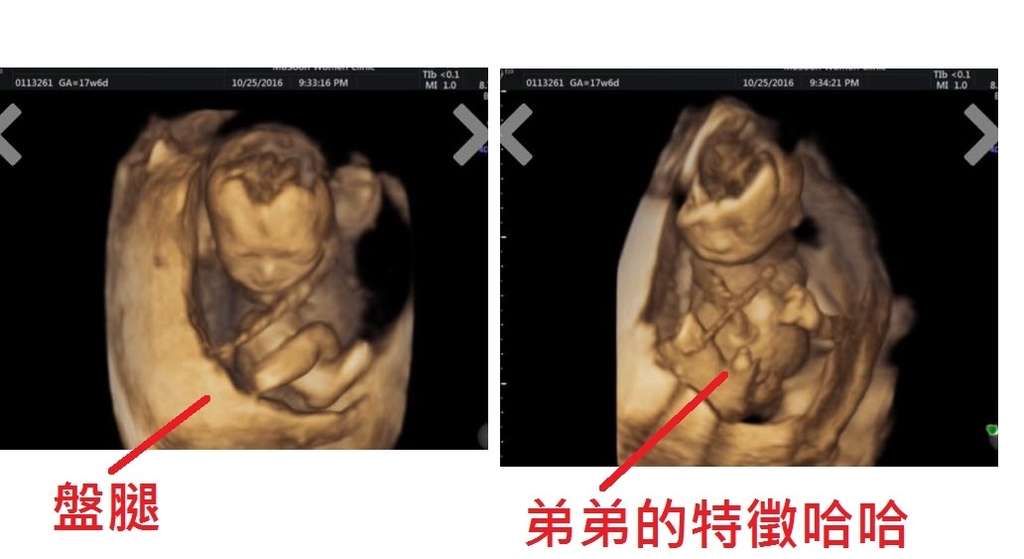

17W6D來到第二次李木生產檢

接著一樣由技術師進行超音波檢查

技術師開始邊解釋邊照,結果寶寶超級乖盤腿坐好在等我們

一照到他時,腿直接開開,技術師才照幾秒鐘立刻說:「是弟弟啦」

哈哈哈哈哈哈哈實在是太可愛了而且果然是我兒子愛盤腿又愛翹腳